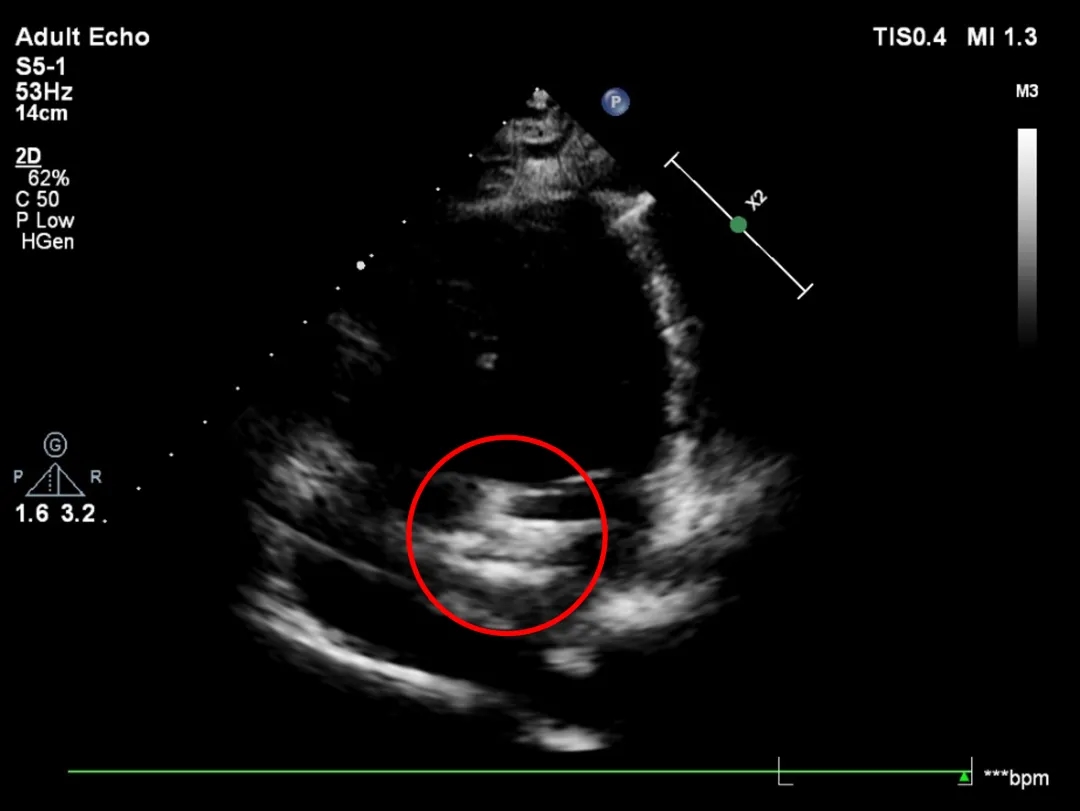

释放后超声

超声下可见室水平和房水平都无残余分流

心脏彩超:心脏超声下可见两个封堵器双盘稳固夹持,无残余分流;

术后1个月心脏超声,房室水平皆无残余分流